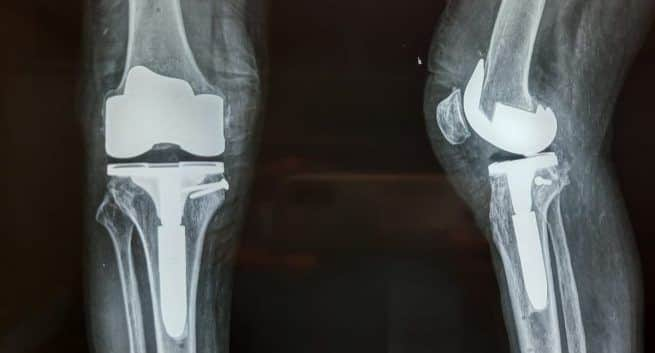

A 64-year-old-man with a history of psoriasis visited the doctors with a 45-degree bow of the knee. He could not walk, and his physical capacity was limited to just five minutes. He was diagnosed with Psoriatic arthritis.

Using the recently advanced technique of robotic knee replacement surgery, doctors at Noble Hospital were able to successfully straighten the patient’s knee. Also Read – Arthritis treatment: Novel 3D technique may improve it

“The patient could walk from the very next day. He could also presume activities such as sitting on the floor, squatting, cycling, stair climbing. The robotic surgery has made him independent. But unfortunately, the other knee is showing similar kinds of tendency and it may have to be operated upon in the near future.” Said Dr Patil.